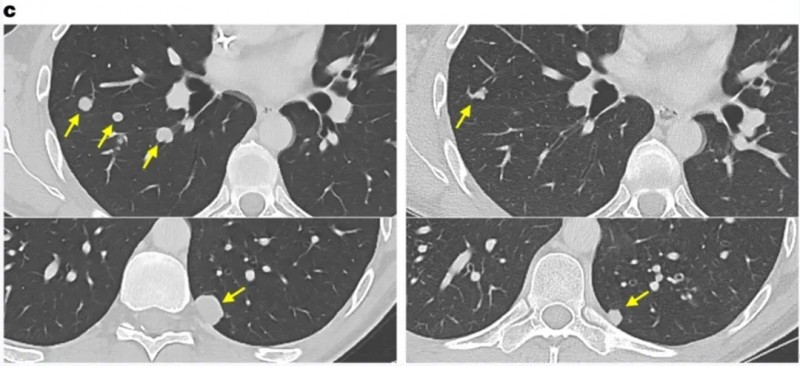

尤为亮眼的是,其中一位合并淋巴结、胸膜及骨转移的晚期肺腺癌患者,在接受GC101回输后,增强CT显示靶病灶缩小36%(达部分缓解PR);且回输后24周内未接受其他治疗,肿瘤仍持续缩小,体现出GC101强大且持久的抗肿瘤活性。下图为该患者接受TIL回输前、治疗6周/12周/18周/24周的CT对比图。

▲图源“JUNCELL”,版权归原作者所有,如无意中侵犯了知识产权,请联系我们删除